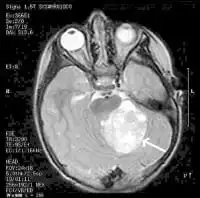

Commonly, migraine-associated changes may be found on MRI results, including white spots or white matter hyperintensities, which appear as bright spots on certain images. These are considered benign findings that do not need to be followed up on with additional scans.

Doctors may bow to patient pressure to obtain a brain scan, and many will practice defensive medicine and order a scan despite the guidelines above. If a scan is ordered to evaluate a headache disorder, doctors prefer MRI with contrast over a CT scan. This is because MRI with contrast is a more sensitive test than CT and does not involve any radiation. However, because MRI with contrast is so sensitive, it often results in abnormal findings unrelated to the headache that may lead to further testing.

The most common abnormalities are small spots in the brain, as mentioned above, that may be mistaken for multiple sclerosis. These spots are seen in up to 30% of all people with migraine, and they are usually an incidental finding with no clinical significance. There are many other common incidental findings that are not associated with migraine but may be a source of increased frustration when they appear on test results.